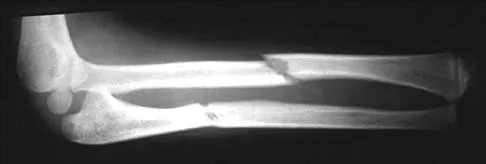

A 44-year-old man who sustained an elbow dislocation 3 months ago now reports pain and restricted elbow motion. Radiographs are shown in Figures 27a and 27b. Management should consist of